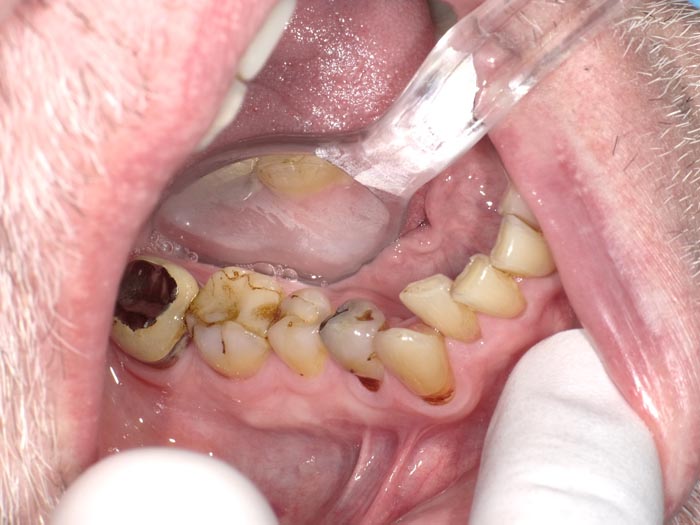

Case 1

A 37-year-old patient presented for treatment after years of neglect. After administering anesthetic and placing an Isolite isolation device, we prepared teeth #10–12 and restored them

with Activa Bioactive-Restorative composite.